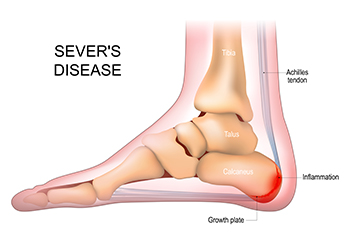

Sever's disease, also known as calcaneal apophysitis, is a common cause of heel pain in growing children, especially those who are active in sports. It occurs when the growth plate in the heel becomes inflamed due to repetitive stress or tension from the Achilles tendon. Symptoms include heel pain during or after physical activity, limping, tenderness at the back of the heel, swelling, and difficulty walking or running. The pain may feel sharp or aching and typically worsens with movement. Sever's disease is most common during growth spurts, often between the ages of eight and 14. A podiatrist can diagnose the condition through a physical examination and a review of the child’s activity level and symptoms. Treatment may include heel supports, stretching exercises, and changes in footwear. If your child is experiencing heel pain during growth, it is suggested that you schedule an appointment with a podiatrist for a proper diagnosis and appropriate care.

Sever’s Disease

Sever’s disease is also known as calcaneal apophysitis, which is a medical condition that causes heel pain I none or both feet. The disease is known to affect children between the ages of 8 and 14.

Sever’s disease occurs when part of the child’s heel known as the growth plate (calcaneal epiphysis) is attached to the Achilles tendon. This area can suffer injury when the muscles and tendons of the growing foot do not keep pace with bone growth. Therefore, the constant pain which one experiences at the back of the heel will make the child unable to put any weight on the heel. The child is then forced to walk on their toes.

Acute pain – Pain associated with Sever’s disease is usually felt in the heel when the child engages in physical activity such as walking, jumping and or running.

Highly active – Children who are very active are among the most susceptible in experiencing Sever’s disease, because of the stress and tension placed on their feet.